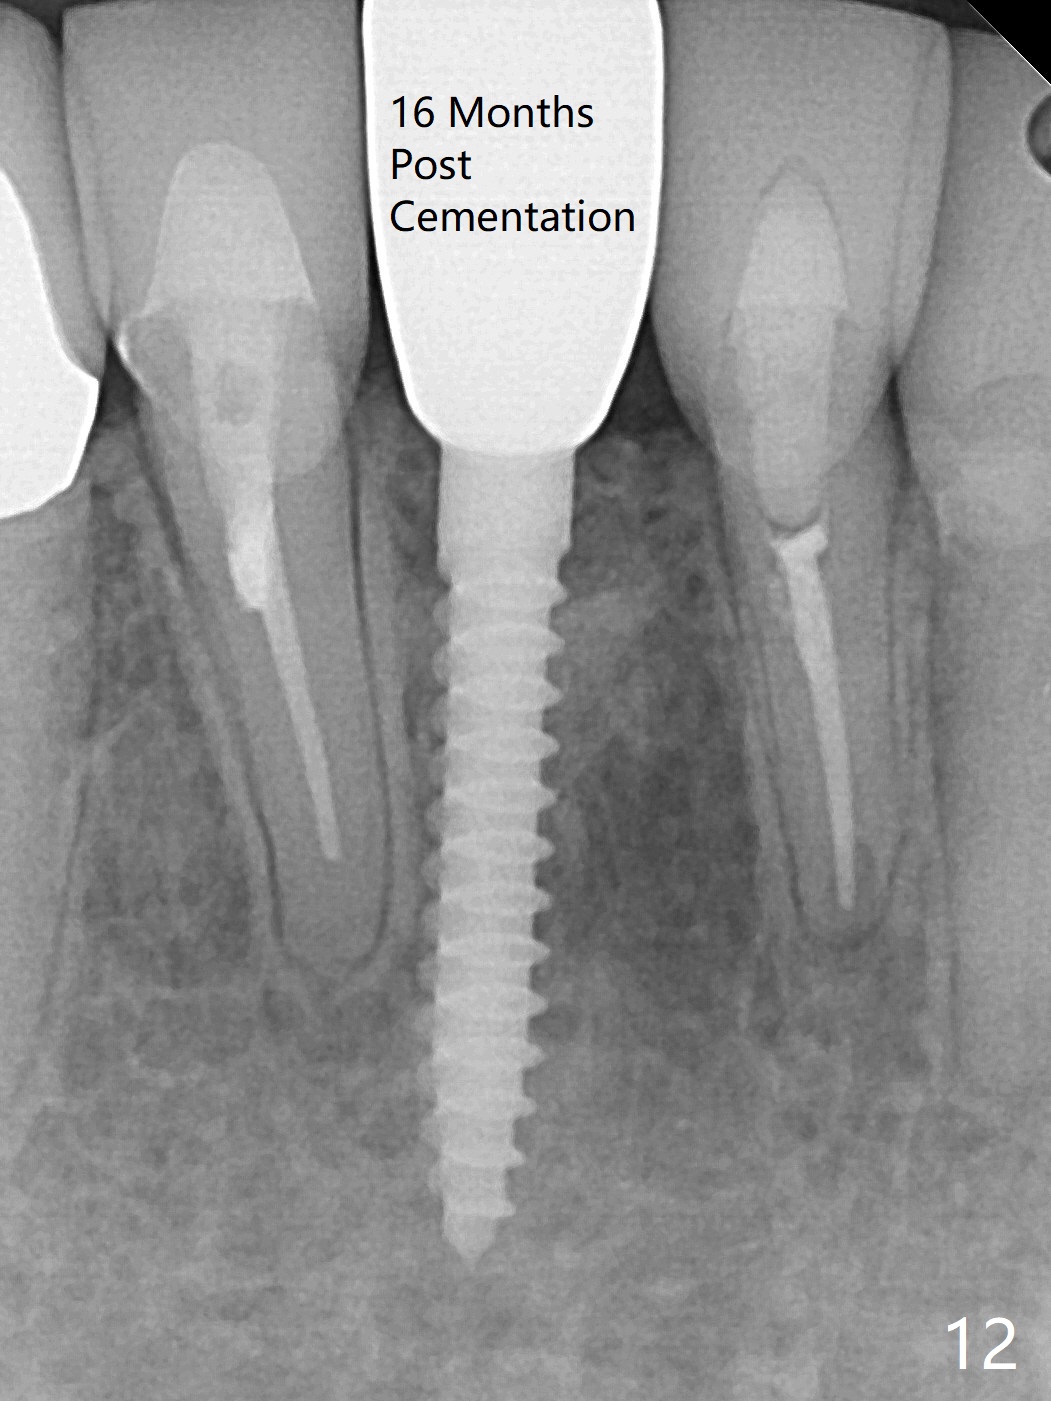

A drawback of implant planning at #25 is not to use a preop PA (Fig.1 (^ fracture line)). The initial trajectory seems to be alright (Fig.2), but a 2.5x14(2) mm implant placed is close to the tooth #26 (Fig.3). In fact the affected tooth is deviated distal; osteotomy should be initiated in the mesial slope of the socket (Fig.4 red line). The final trajectory appears to be perfect (Fig.5). Furthermore the 1st intraop PA should be analyzed carefully (Fig.6). A new osteotomy should be established mesial or the existing one should be moved mesial with Lindamann bur (Fig.7). The distal implant placement may be related to more bone loss in the distal crest 3.5 months postop (Fig.8) and more severe distal papillary recession (Fig.9 *). The bone density increases at the levels of the non-thread and thread portions of the implant (in the original socket) nearly 10 months post cementation (Fig.11 *, <). There is no bone loss 16 months post cementation (Fig.12).